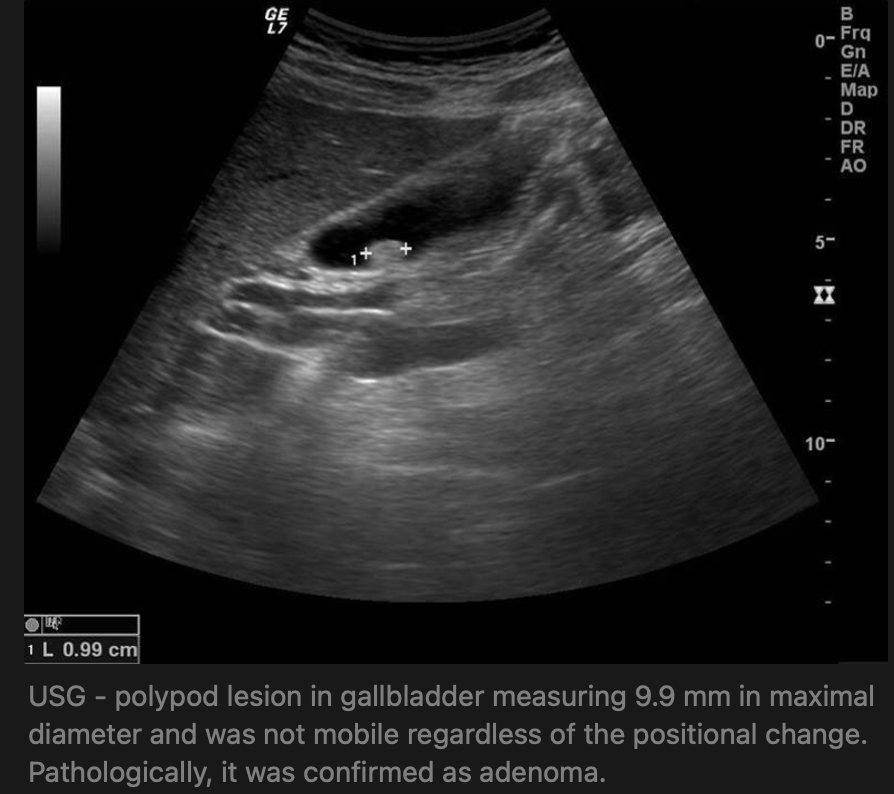

USG - features of GB polyps:

• specificity (71–98%) and sensitivity (50–90%)

• hyperechoic lesions protruding into the GB lumen,

• absence of post-acoustic shadow,

• lack of positional change of lesions,

• crucial to identify the size, number, and shape of polyps, GB wall thickening, and presence of gallstones.

• sometimes, biliary sludge, or small stones (<5 mm), can be mistaken as GB polyps.

• Prevalence 3-10% in healthy patients on ultrasound

• US alone cannot determine whether polyp is a neoplastic or nonneoplastic polyp. Therefore, once GB polyps are incidentally identified using US, surgical treatment is frequently being considered if the size is larger than 1 cm.